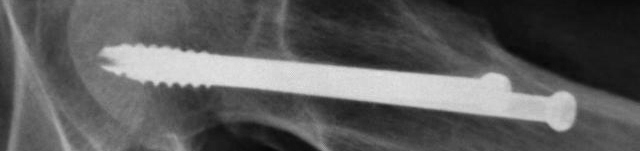

股骨颈骨折采取钢钉固定,若已达到愈合标准可以取出钢钉。这需要住院手术,毕竟需要麻醉,一般三五天,最快两三天即可出院。

如决定入院取出钢钉,需要做好相应的术前准备,包括抽血化验:血常规、尿常规、肝功肾功、血糖、电解质、肝炎系列、艾滋梅毒、凝血功能等,这些在早晨6点钟空腹采血;检查:患部X线、胸部X线、心电图。

如无特殊情况,当天即可安排手术,局麻或腰麻下取出钢钉。术后会密切观察病情,如无异常第二天即可办理出院。